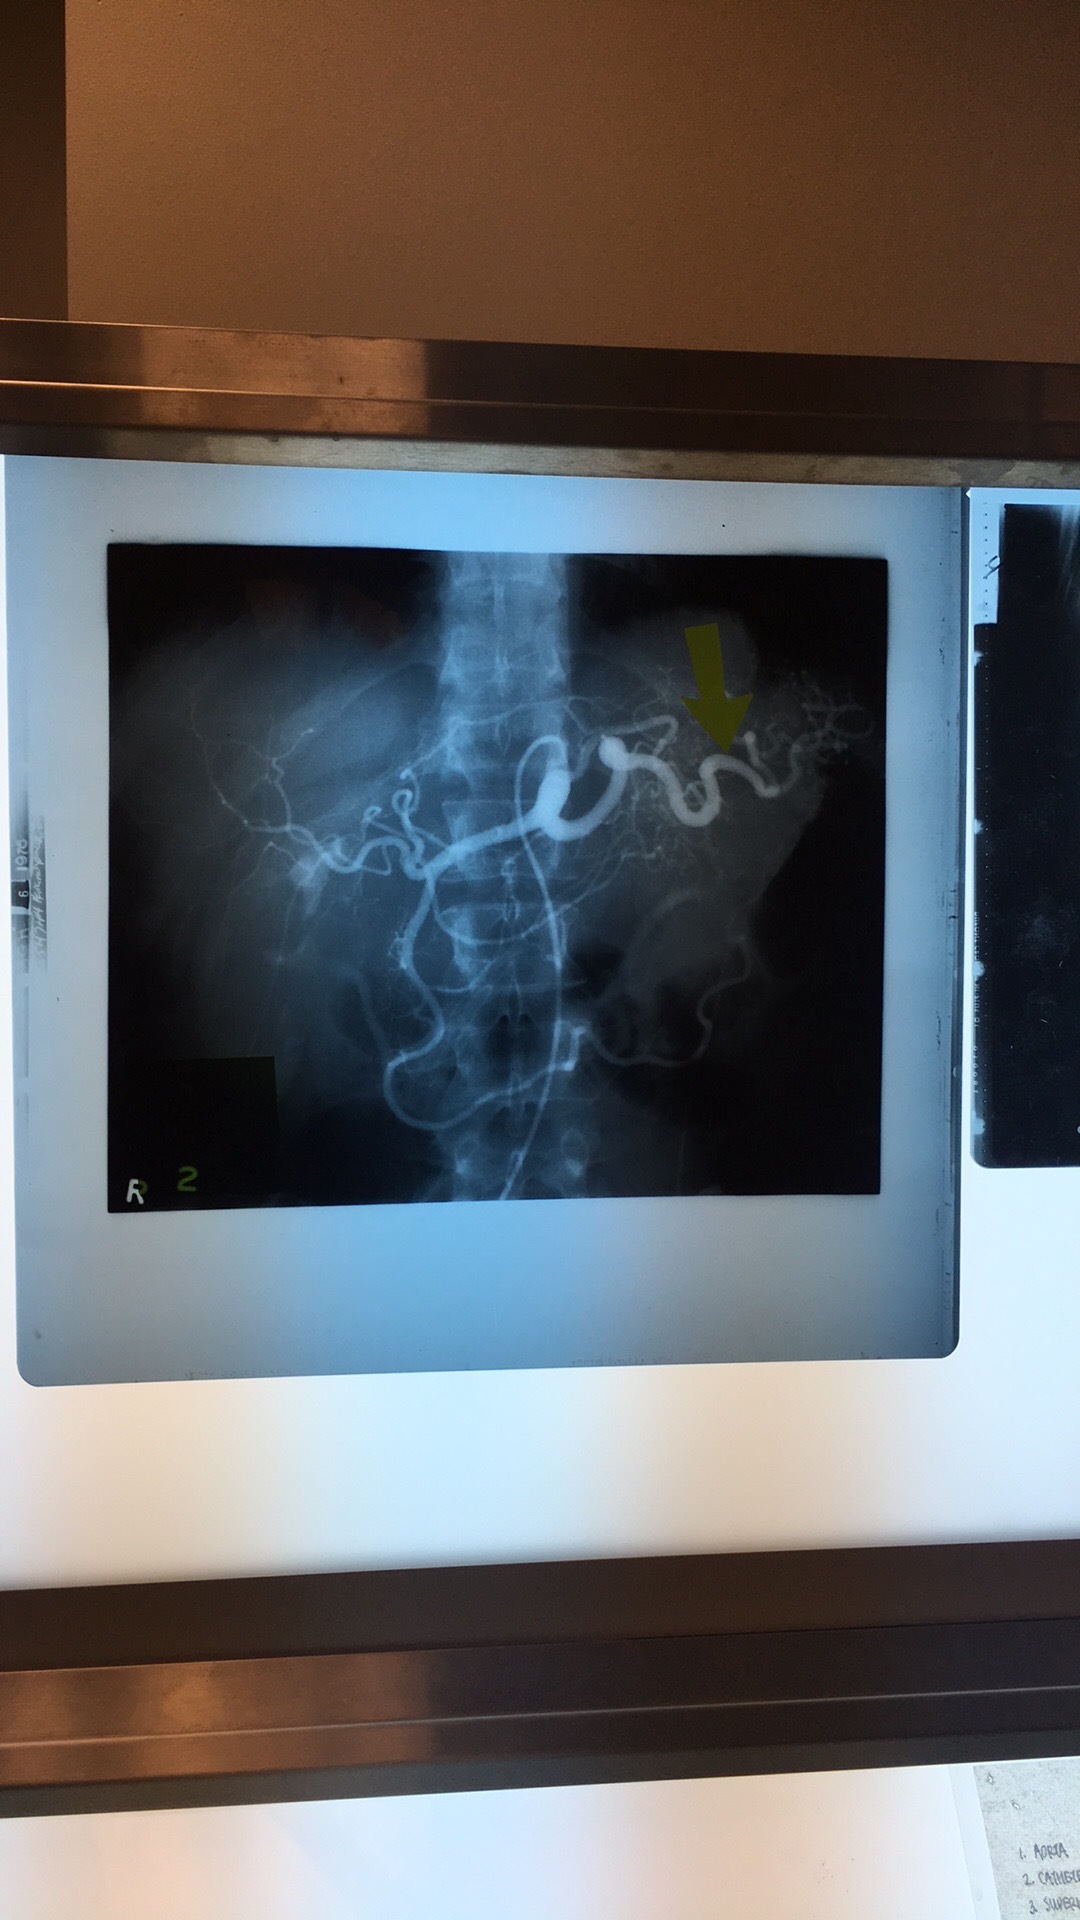

Which artery? What are the 5 branches?

Superior Mesenteric Artery. Intestinal Arteries, Right Colic Art, Middle Colic Art, Ileocolic Art, Inferior Pancreaticoduodenal Art